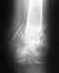

14.01.2015 выполнена операция- закрытая репозиция,остеосинтез большеберцовой кости левой голени штифтом с блокированием.Проходил 4 месяца с шурупами не выкручивали.А 19.05.2015 пытались выкрутить шуруп который фиксирует, не получилось. Заведующий сказал так ходить до конца. А когда будут удалять штифт так да и удалят шуруп. Вопрос правильно это ? можно так ходить и срастется кость правильно с блокирующим болтом он не будет мешать. Что делать? Помогите?

Снимки покажите.